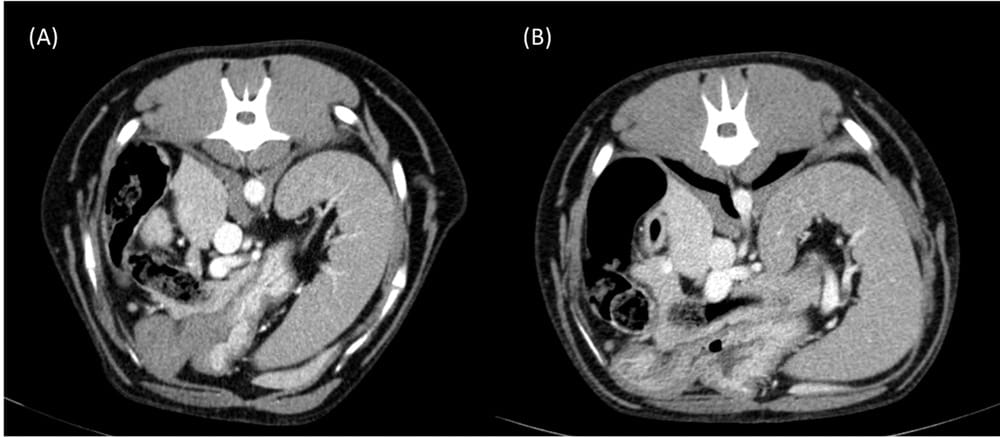

Transverse abdominal CT images obtained at the level of the celiac artery during the portal venous phase in the study dosed according to A, TBW and B, LBW. This patient was scored as having excellent contrast enhancement in all the assessed organs and vessels by both radiologists in the studies dosed according to TBW and LBW. Collimation thickness: 1.2 mm; interval index: 1.5 mm; pitch: 1.3; tube rotation time: 0.6 s; mA: 55 kVp: 110; soft tissue window width: 350 HU, level: 40 HU